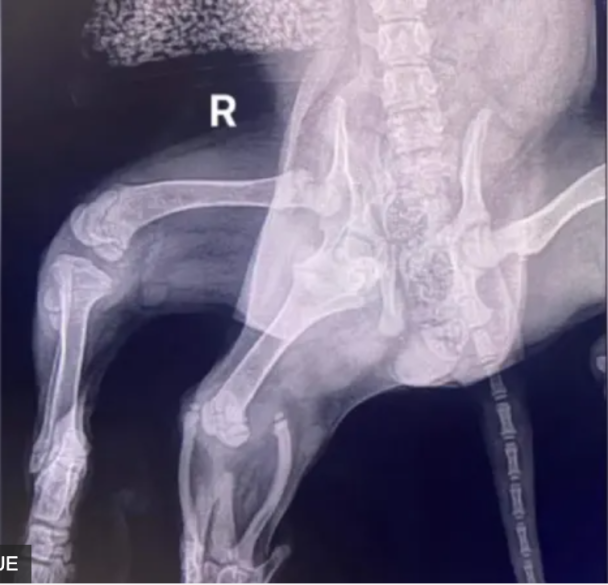

У Великій Британії ветеринари провели успішну операцію з ампутації зайвих кінцівок спаніелю по клицчі Аріель, у якої була вроджена вада – шість лап.

Хірургам також вдалося врятувати всі чотири "нормальні" кінцівки собаки. Адже були побоювання, що одну з них також доведеться ампутувати.

Майкі Лолор є засновником і керівником зоозахисної організації Greenacres Rescue поблизу Гаверфордвеста, який прийняв Аріель після того, як її виявили на вулиці самотньою, схудлою і наляканою, розповів, що комп’ютерна томографія показала, що у Аріель лише одна нирка, збільшила складність необхідного медичного лікування.

"Через наявність двох тазостегнових суглобів з одного боку таз Аріель так і не сформувався належним чином. У результаті її звичайна задня права лапа практично не мала м’язового тонусу, тож існувала ймовірність, що її також доведеться ампутувати", - пояснив Майкі Лолор.

За його словами, на щастя, ампутація потрібної кінцівки не знадобилася, вона останнім часом зміцнилася.

Аріель назвали на честь персонажа діснеївської "Русалоньки", тому що її частково зрощені додаткові лапи нагадували хвіст русалки.